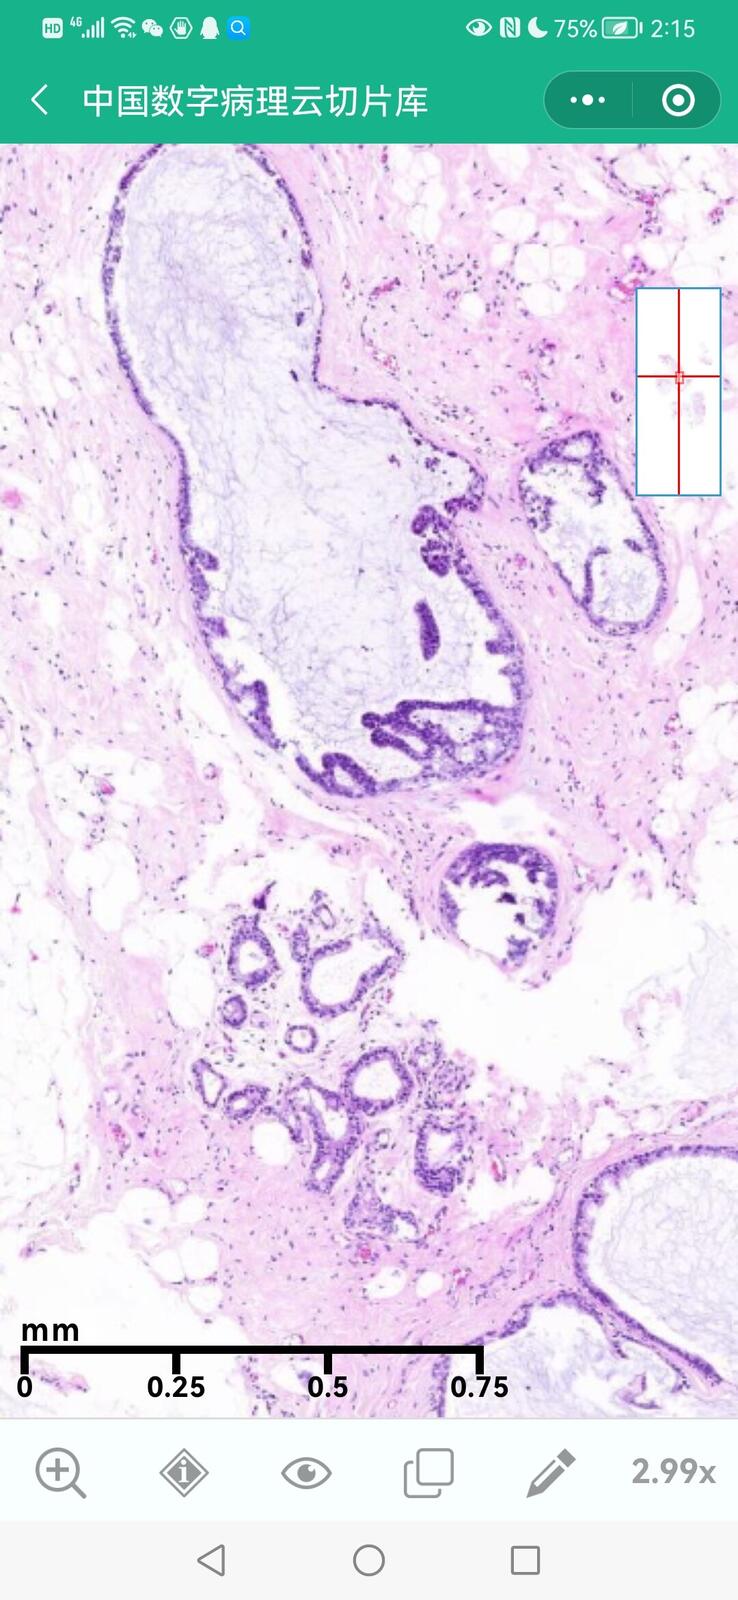

乳腺黏液性囊腺瘤伴导管内癌